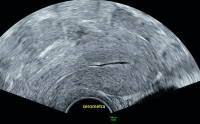

Ultraschall-Serometra

Abbildung 4: HyCoSy, die iatrogene Serometra: Links im Bild ist deutlich der Katheter sichtbar, mit dem das echoarme NaCl ins Cavum uteri eingebracht wird.

Keywords: Cavum uteriGynäkologieHyCoSyKatheterSerometraSonographieUltraschall